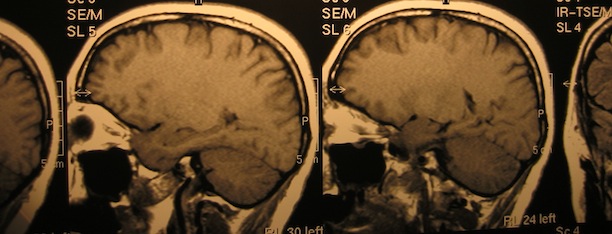

Memories As Chemicals

Discover magazine has a fascinating article in the July/August 2009 issue called “Out of the Past” by Kathleen McGowan, discussing the changes in memory study. I’d link it here, but it’s not up on the Discover site yet (if it ever will be). First, I’ll preface this by reminding everyone that we’re made up of […]